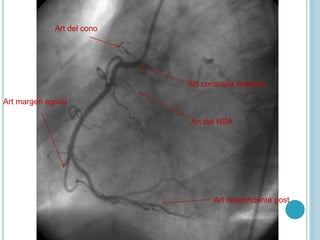

Art coronaria derecha

Art descendente post

Art margen agudo

Art del cono

Art del NSA

Art coronaria derecha Artdescendente post Art margen agudo Art del cono Art del NSA